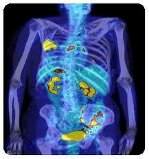

Nükleer tıpta, kullanılan radyofarmotikler belirli organlara, kemik veya dokulara bağlanır, yayınlanan alfa, beta ve gama ışınları özel dedektörler ile dedekte edilebilir. Bu detektörler bilgisayarla birlikte çalışarak vücutta hastalık tanısında kullanılırlar.

· Tc99m MDP: kemik sintigrafisi